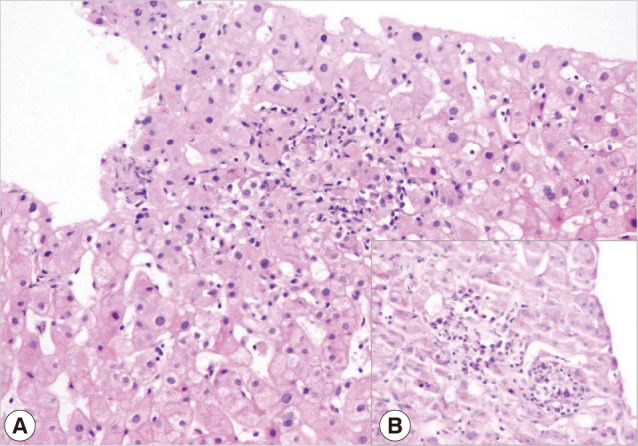

A 26-year-old female patient referred to the rheumatology department with complaints of anorexia, malaise, weight loss, joint swelling, and low grade fever. She was living in a Mediterranean region of Turkey. Her past history was notable for photosensitivity, oral ulcers, and possible thalassemia trait. On admission, her physical examination was significant for erythema and symmetrical arthritis at ankles, wrists, and hand joints. The spleen was palpated 10 cm below the costal margin, and the liver had a longitudinal size of 15 cm. Erythrocyst sedimentation rate (ESR) and C- reactive protein was 65 and 19.9 mg/L, respectively. Complete blood count revealed hemoglobin 10.2 gr/dl, mean corpuscular volume 69 fl, leukocyte 4,000/mm3, and platelet 157,000/mm3. Other pertinent laboratory data was as follows: creatinine 0.7 mg/dl (Normal=0.5-1.2), alanine aminotransferase 46 U/L (ALT, Normal<40), aspartate aminotransferase 51 U/L (AST, Normal<40), alkaline phosphatase 67 U/L (ALP, N=53-141), gama-glutamyl transferase 17 U/L (GGT, N=0-50), albumin 3.2 g/dl, globulin 6.9 g/dl, and lactate dehydrogenase 236 U/L (N=125-243). Her laboratory investigation was positive for anti-nuclear antibody immunofluorescence (ANA-IFA), anti-smooth muscle antibody (ASMA), and Coombs tests on previous referral center. Repeated ANA was strongly positive as well as antimitochondrial (AMA-M2) antibodies and Coombs tests. Rheumatoid factor (RF) was 123 IU/ml (N<20). Liver kidney microsomal (anti-LKM), anti-cytosolic liver (LC-1), antisoluble liver/liver-pancreas (SLA/LP), ASMA, anti-ENA, ds-DNA tests were negative. Serum C3 and C4 were within normal limits. IgG was 5,810 mg/dl (N=751-1,560) with a polyclonal pattern. A liver biopsy was performed to rule out autoimmune hepatitis. Histological examination of the liver biopsy revealed robust plasma cell and lymphocyte infiltrations in the sinusoidal areas, and periductal and portal small granuloma formation. Histochemically, plasma cells, which were stained for Methyl Grün Pyronine (MGP), were found to act as a dominant feature among the inflammatory infiltrates in the liver. This finding also supported and raised the suspicion of autoimmune hepatitis-PBC overlap (Fig. 1A, B).

Fig. 1

(A) Indirect cholestatic features with lobular confluent necrosis (H&E stain, ×200). (B) Plasma cells as a dominant component of inflammation in the liver (MGP, ×400)

Fig. 1 (A) Indirect cholestatic features with lobular confluent necrosis (H&E stain, ×200). (B) Plasma cells as a dominant component of inflammation in the liver (MGP, ×400)